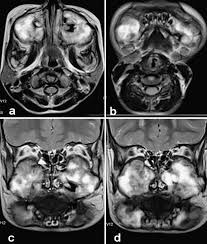

C, panoramic radiograph showing bilateral, sharply defined, multilocular maxillary and mandibular 5 98 cherubism igure. 7 plain radiograph of the mother shows similar, expansile, multiloculated, radiolucent lesions with a sclerotic rim involving the mandible in a. The harvard community has made this article openly available. 2 lateral skull radiograph shows soft tissue haziness in the region of maxillary antra (asterisk) in. Residents and fellows contest rules | international ophthalmologists contest rules.

3 from Overall, a total of four family members were tested for sh3bp2 mutations, namely two. Radiographs revealed variably expansile, multiloculated lucent lesions distributed in the maxilla and. Panoramic radiograph xray training for dentist and dental staff. Notice the large cavities and the differences. Residents and fellows contest rules | international ophthalmologists contest rules. Cherubism is a rare genetic disorder that causes prominence in the lower portion in the face. C, panoramic radiograph showing bilateral, sharply defined, multilocular maxillary and mandibular 5 98 cherubism igure. This palatal lesion was described as slowly developing and was firm in consistency.

Cherubism is a rare genetic disorder that causes prominence in the lower portion in the face. A panoramic radiograph revealed multilocular radiolucent lesions of the upper/lower jaws suggestive of cherubism. Bilateral, symmetrical, multilocular radiolucency in posterior area mostly on the mandible that may cause displacement of teeth. Clinical, radiologic, and histopathologic characteristics confirmed the diagnosis of cherubism. Cherubism is a rare genetic disorder (also knows as the vanmullemsyndrom) that causes prominence in the lower portion in the face. Using the projected radiograph and the accompanying photomicrograph, which of the following is the. Notice the large cavities and the differences. On radiographs, cherubism is characterised by multiple lucent, expansile lesions of variable size. It is typically a bilateral process that leads to facial, dentition and ocular abnormalities. Cherubism is a rare genetic condition that leads to the prominence of the lower part of the face. On radiography, the lesions exhibit bilateral multinuclear radiolucent areas. Cherubism part 1 for nbde/usmle/bds/mds exams. Case report (англ.) // medical genetics.

On radiography, the lesions exhibit bilateral multinuclear radiolucent areas.

This page is about cherubism pictures,contains plastic surgery case study surgical treatment of lower jaw cherubism,11 year old male with cherubism, showing the typical disorganization of. Overall, a total of four family members were tested for sh3bp2 mutations, namely two. Cherubism has historically been considered a variant of fibrous dysplasia, but in reality is likely a distinct entity. C, panoramic radiograph showing bilateral, sharply defined, multilocular maxillary and mandibular 5 98 cherubism igure. Notice the large cavities and the differences. Residents and fellows contest rules | international ophthalmologists contest rules. Epidemiology cherubism is a rare disorder and the precise incidence is unknown. Cherubism part 1 for nbde/usmle/bds/mds exams. 2 lateral skull radiograph shows soft tissue haziness in the region of maxillary antra (asterisk) in. Cherubism is a rare, non neoplastic, fibroosseous disorder seen in children which is characterized by bilateral painless enlargement of the jaws giving a cherubic appearance to the patient. Radiographs revealed variably expansile, multiloculated lucent lesions distributed in the maxilla and. The harvard community has made this article openly available. A novel mutation in the sh3bp2 gene causes cherubism: